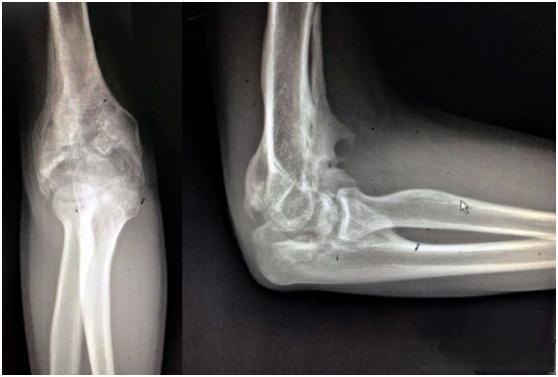

肘关节僵硬是肘关节创伤后的常见并发症之一,严重影响患者的生活质量。泉州市正骨医院上肢科医疗学科带头人郭颖彬主任指出,当肘关节活动范围受限50%时,整个上肢功能将丧失80%。这意味着,即使是一个看似简单的屈肘动作,也可能让患者面临巨大的挑战。

肘关节僵硬的原因多种多样,主要包括肘关节骨折、脱位等创伤性因素,以及类风湿性关节炎、骨关节炎等非创伤性因素。长期制动或不当锻炼也可能导致肘关节活动受限。这种状况不仅影响日常活动,如开门、吃饭、接电话等,还可能导致患者无法独立完成穿衣等基本生活动作。